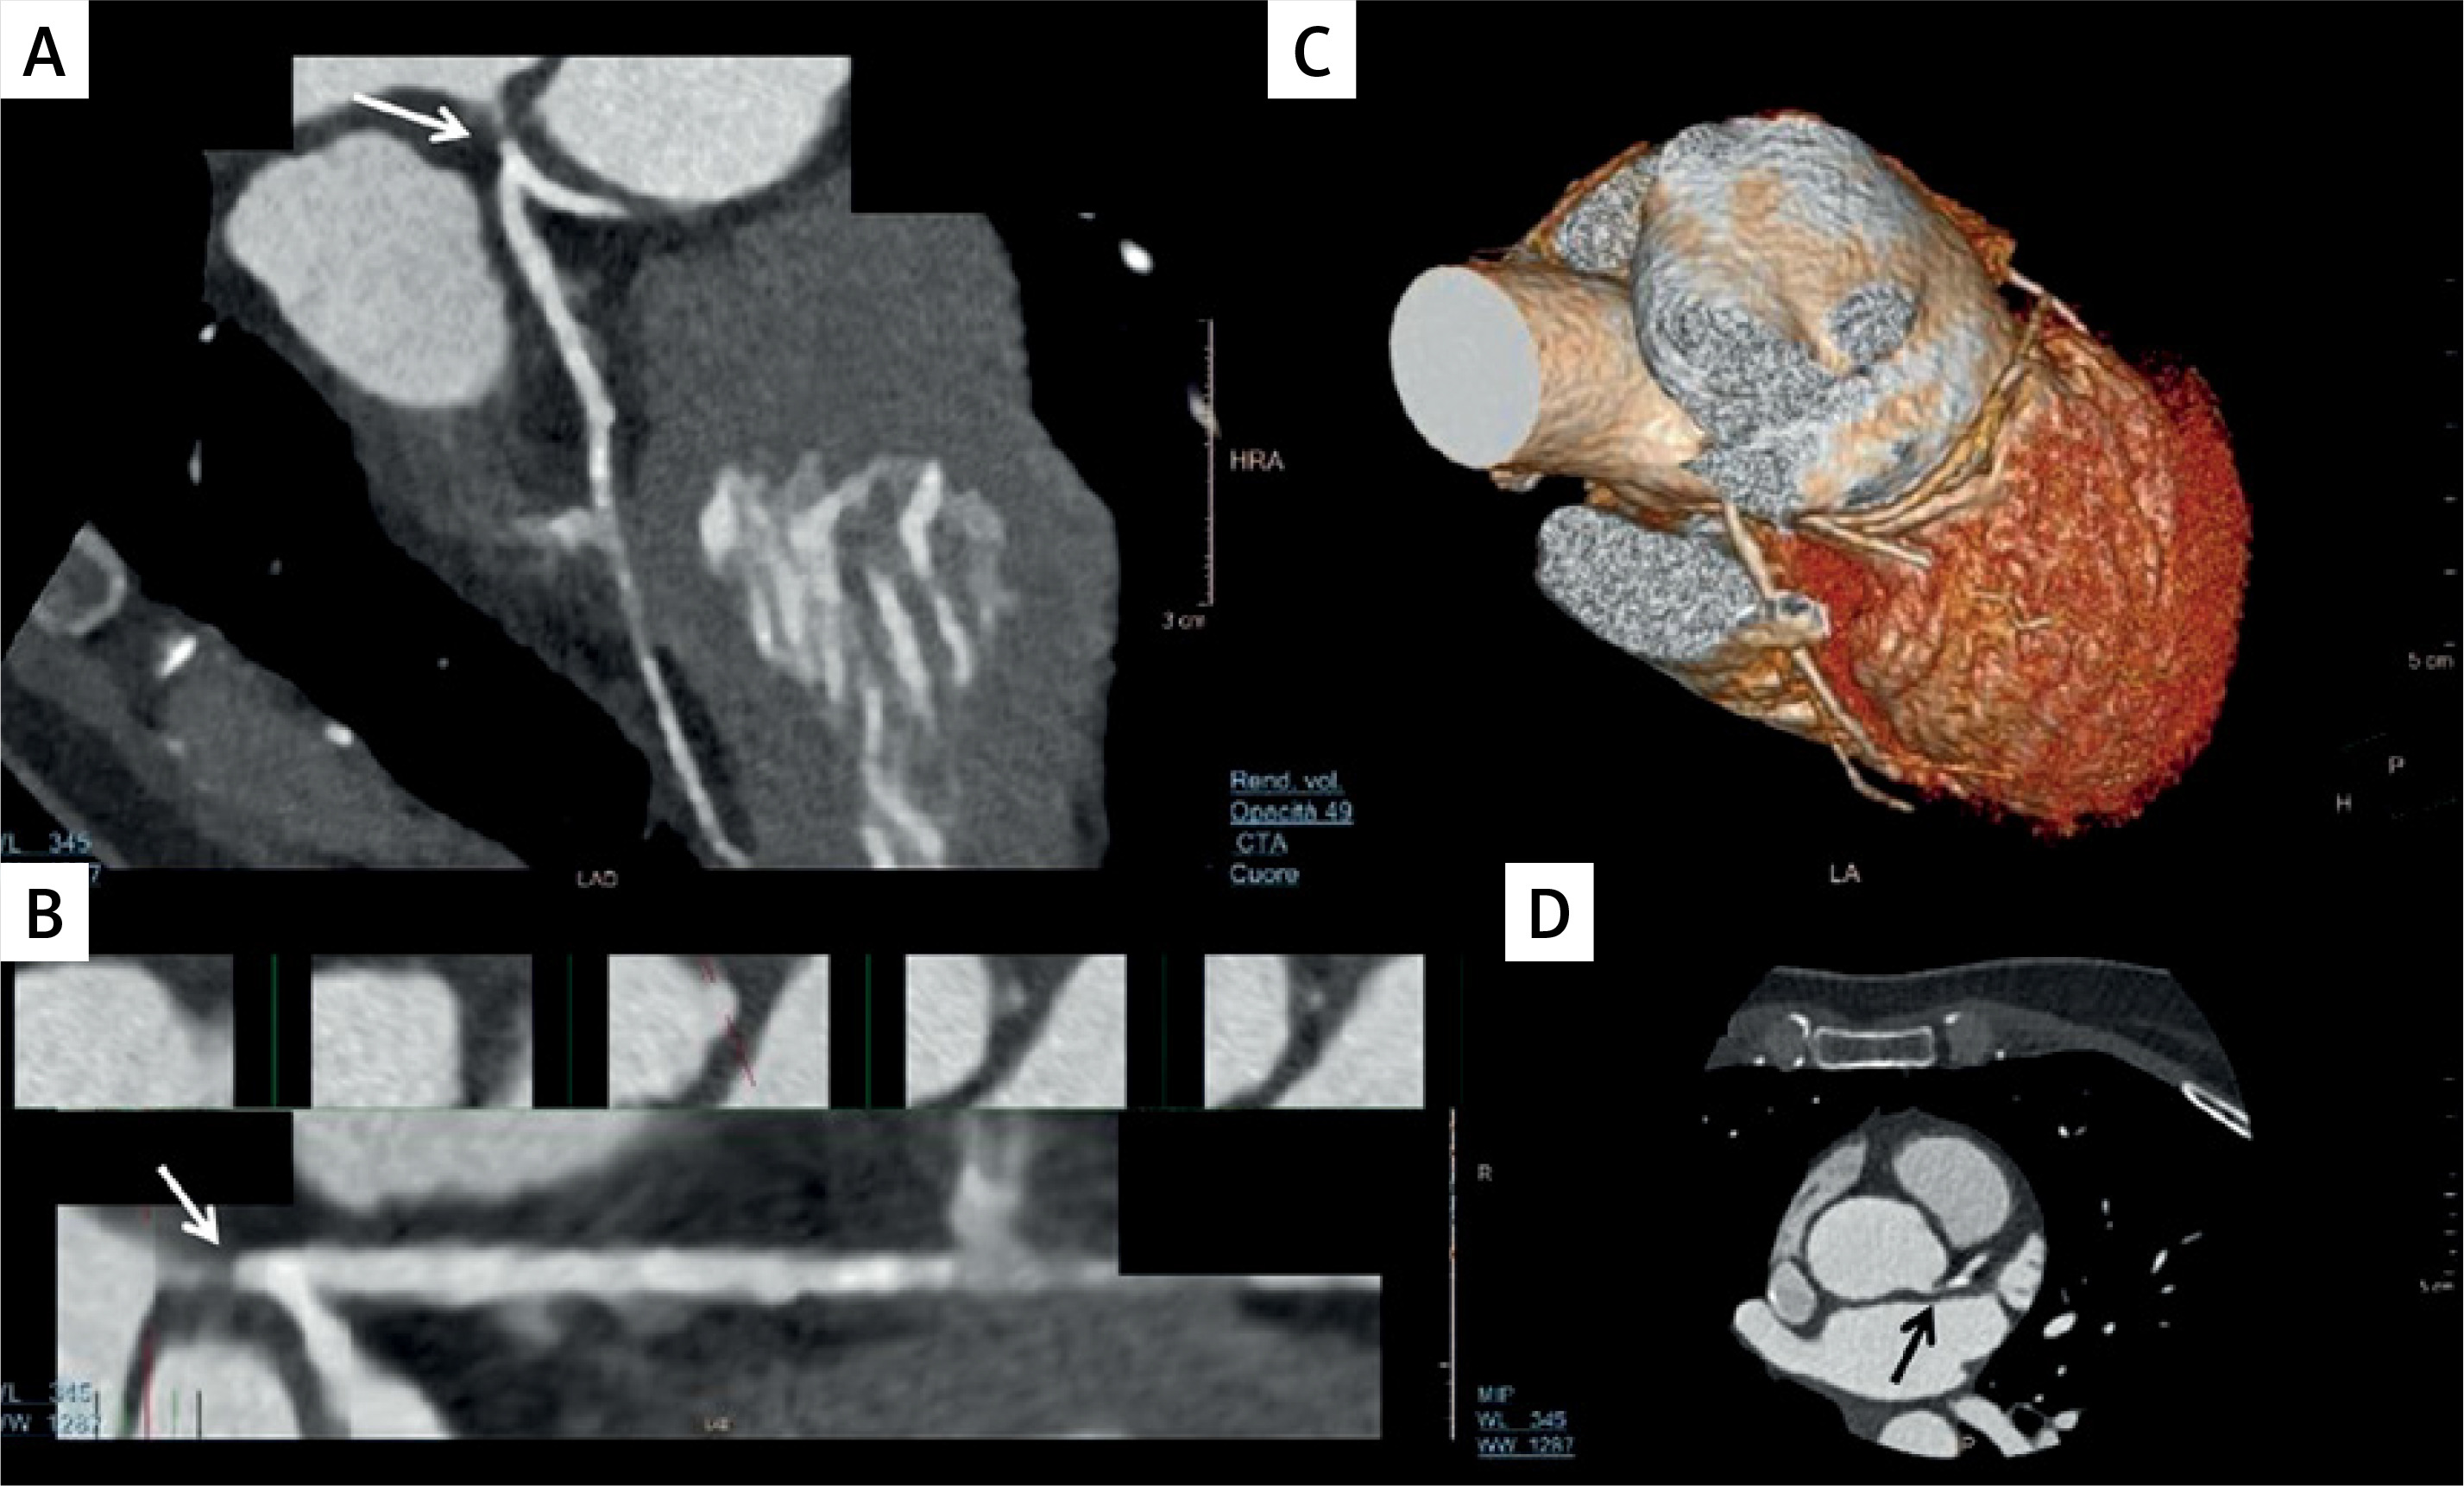

In addition to quantifying coronary stenoses, CCTA has the capability to characterize coronary atherosclerosis with the visual identification and discrimination of high-risk plaques that correlate with adverse prognostic features [37]. As shown in Figure 1, the plaque vulnerability is characterized by the following features, which have prognostic implications [38]: (i) a positive remodeling (an outer vessel diameter 10% greater than the mean diameter of the segments immediately proximal and distal to the plaque); (ii) low-attenuation plaque (a focal central area of plaque with an attenuation density of < 30 Hounsfield units); (iii) spotty calcification (a focal calcification within the coronary artery wall that measures < 3 mm in maximum diameter); (iv) napkin-ring sign (a central area of low-attenuation plaque with a peripheral rim of high attenuation) [14].

Figure 1

Features associated with plaque vulnerability assessed by coronary computed tomography (CT). From top to bottom the pictures show (A) a positive remodeling: the arrow indicates the classical outward plaque expansion; (B) a low attenuation plaque: the arrow indicates the plaque with a CT attenuation of 5 HU (Hounsfield units), thus a lipid-rich one (a CT attenuation value of < 30 HU indicates a lipid-rich plaque); (C) a spotty calcification: calcium deposits with a size of < 3 mm are indicated by the arrow; (D) a napkin-ring sign: the attenuation region, surrounded by a higher-attenuation ring (pointed by arrow), is characterized by a necrotic core surrounded by a fibrous cap